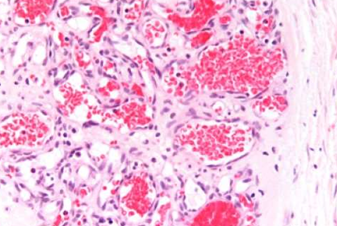

Vascular neoplasm: Malignant

Angiosarcoma

.Highly malignant tumor of endothelial origin.

.Site: liver

.Gross: Large, hemorrhagic, necrotic mass.